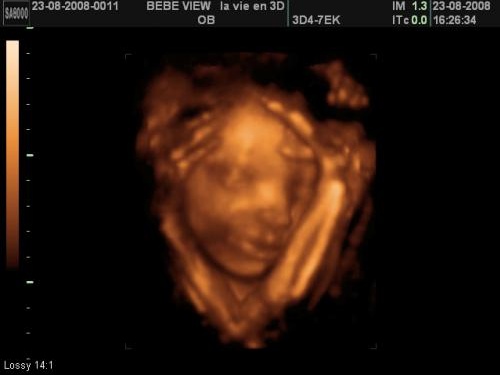

Je suis allez aujoud hui faire une echo 3D a toulouse , et je suis vraiment super contente Ca a été un moment magique pour le papa et moi Bon seule petit hic c es qu elle etait tres mal placé donc on a pas pu voir son visage de face, mais on es tres content quand meme Pour les papas c es encore plus magic que pour nous , ils arrivent enfin a voir leur bébé La première échographie obligatoire a lieu aux alentours de 12 semaines d'aménorrhéePour l'échographie du 2e trimestre et l'échographie du 3e trimestre, il faudra attendre respectivement la 22e puis la 32e semaine d'aménorrhéeL'échographie est une technique d'imagerie médicale utilisant des ultrasons qui permettent de visualiser le fœtusDans les trisomies 21 libres, la naissance d'un premier enfant trisomique 21 avant l'âge de 30 ans, majore légèrement le risque pour les grossesses suivantes (risque de récurrence 1 à 2 %), alors que pour les femmes ayant eu leur premier enfant trisomique après 30 ans, le risque ne serait pas augmenté (translocations et mosaïques exclues) Trisomie 21 par translocation (4 % à 4,8 %

Echographie 3D le prix, les risques et le meilleur moment Depuis de nombreuses décennies, les progrès de la médecine et des explorations fonctionnelles ont considérablement amélioré la surveillance des grossesses C'est pourquoi ont été rendues obligatoires les trois échographies au cours des neuf mois de gestation, faites par unL'échographie 3D repose sur la même technique que l'échographie classique, à savoir l'utilisation des ultrasons Ces ultrasons se propagent et se réfléchissent à travers le corps, etEt on a eu une echo 3D de sa petite tête !